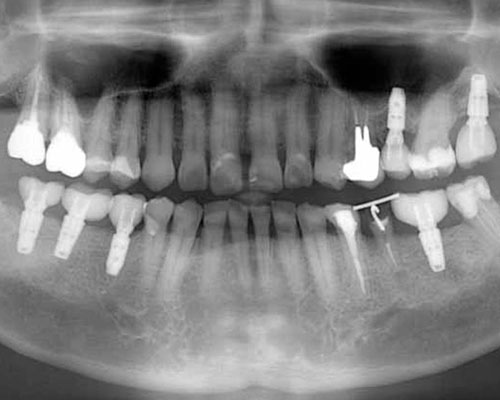

3本目のインプランと左下のブリッジに問題発生

やっと右下にセラミックの歯が入りました。左上にも3本目のインプラントを入れ、もう1本の割れた歯を抜きました。しかし、レントゲンをよく見てみると左側を酷使していた為か、ブリッジの下に虫歯ができて怪しくなっています。